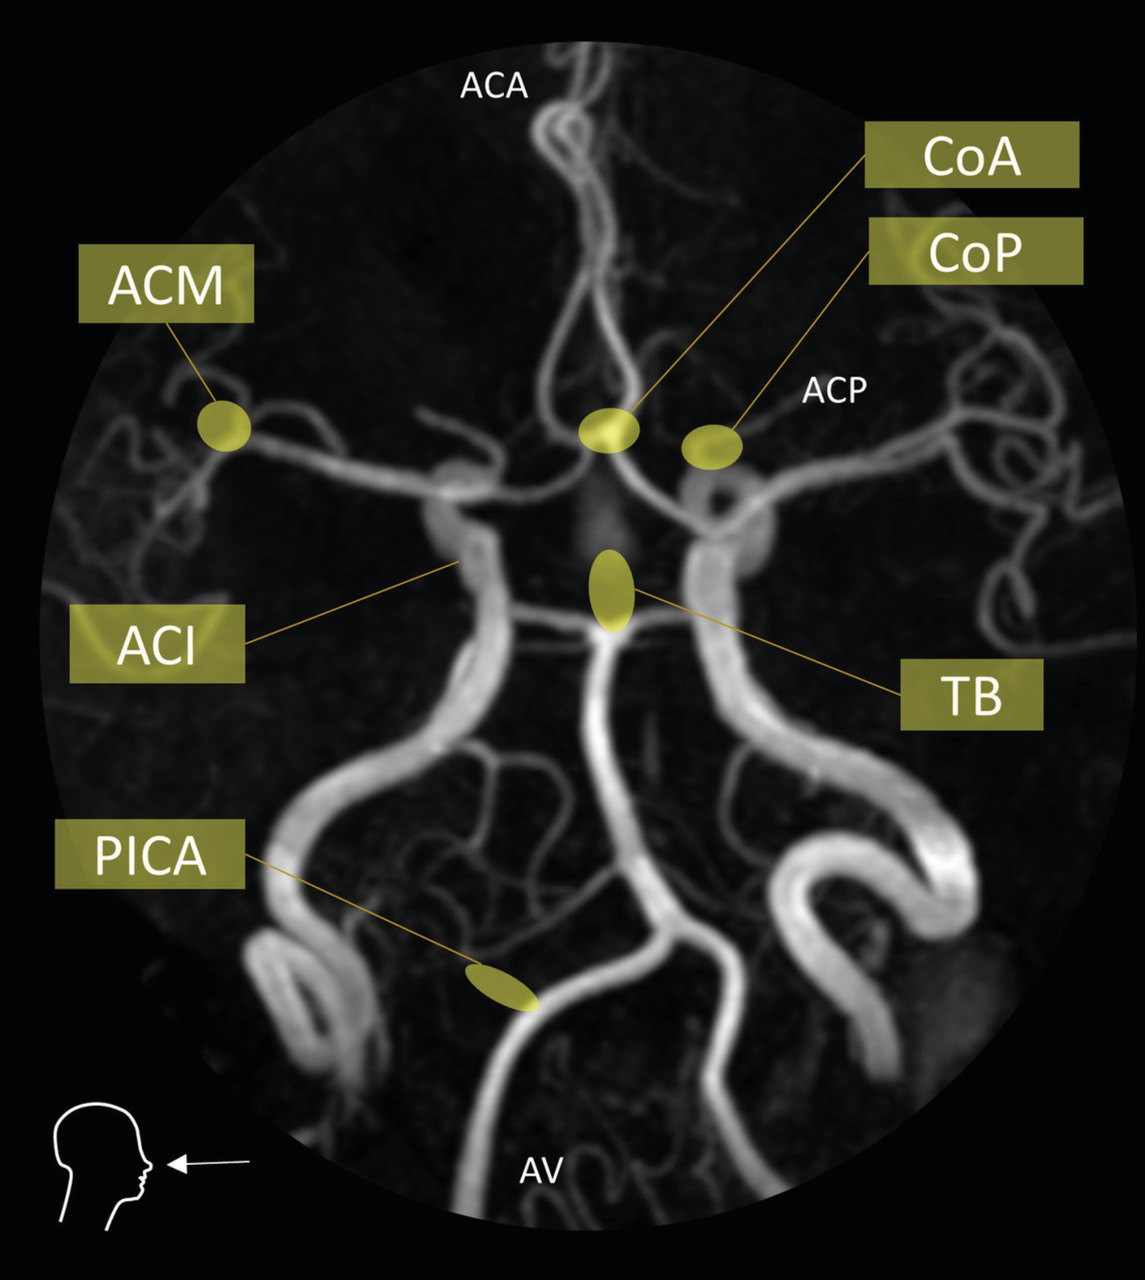

L’angiographie digitale permet de planifier et de suivre le traitement lorsqu’il est réalisé par voie endovasculaire. (fig. 4)